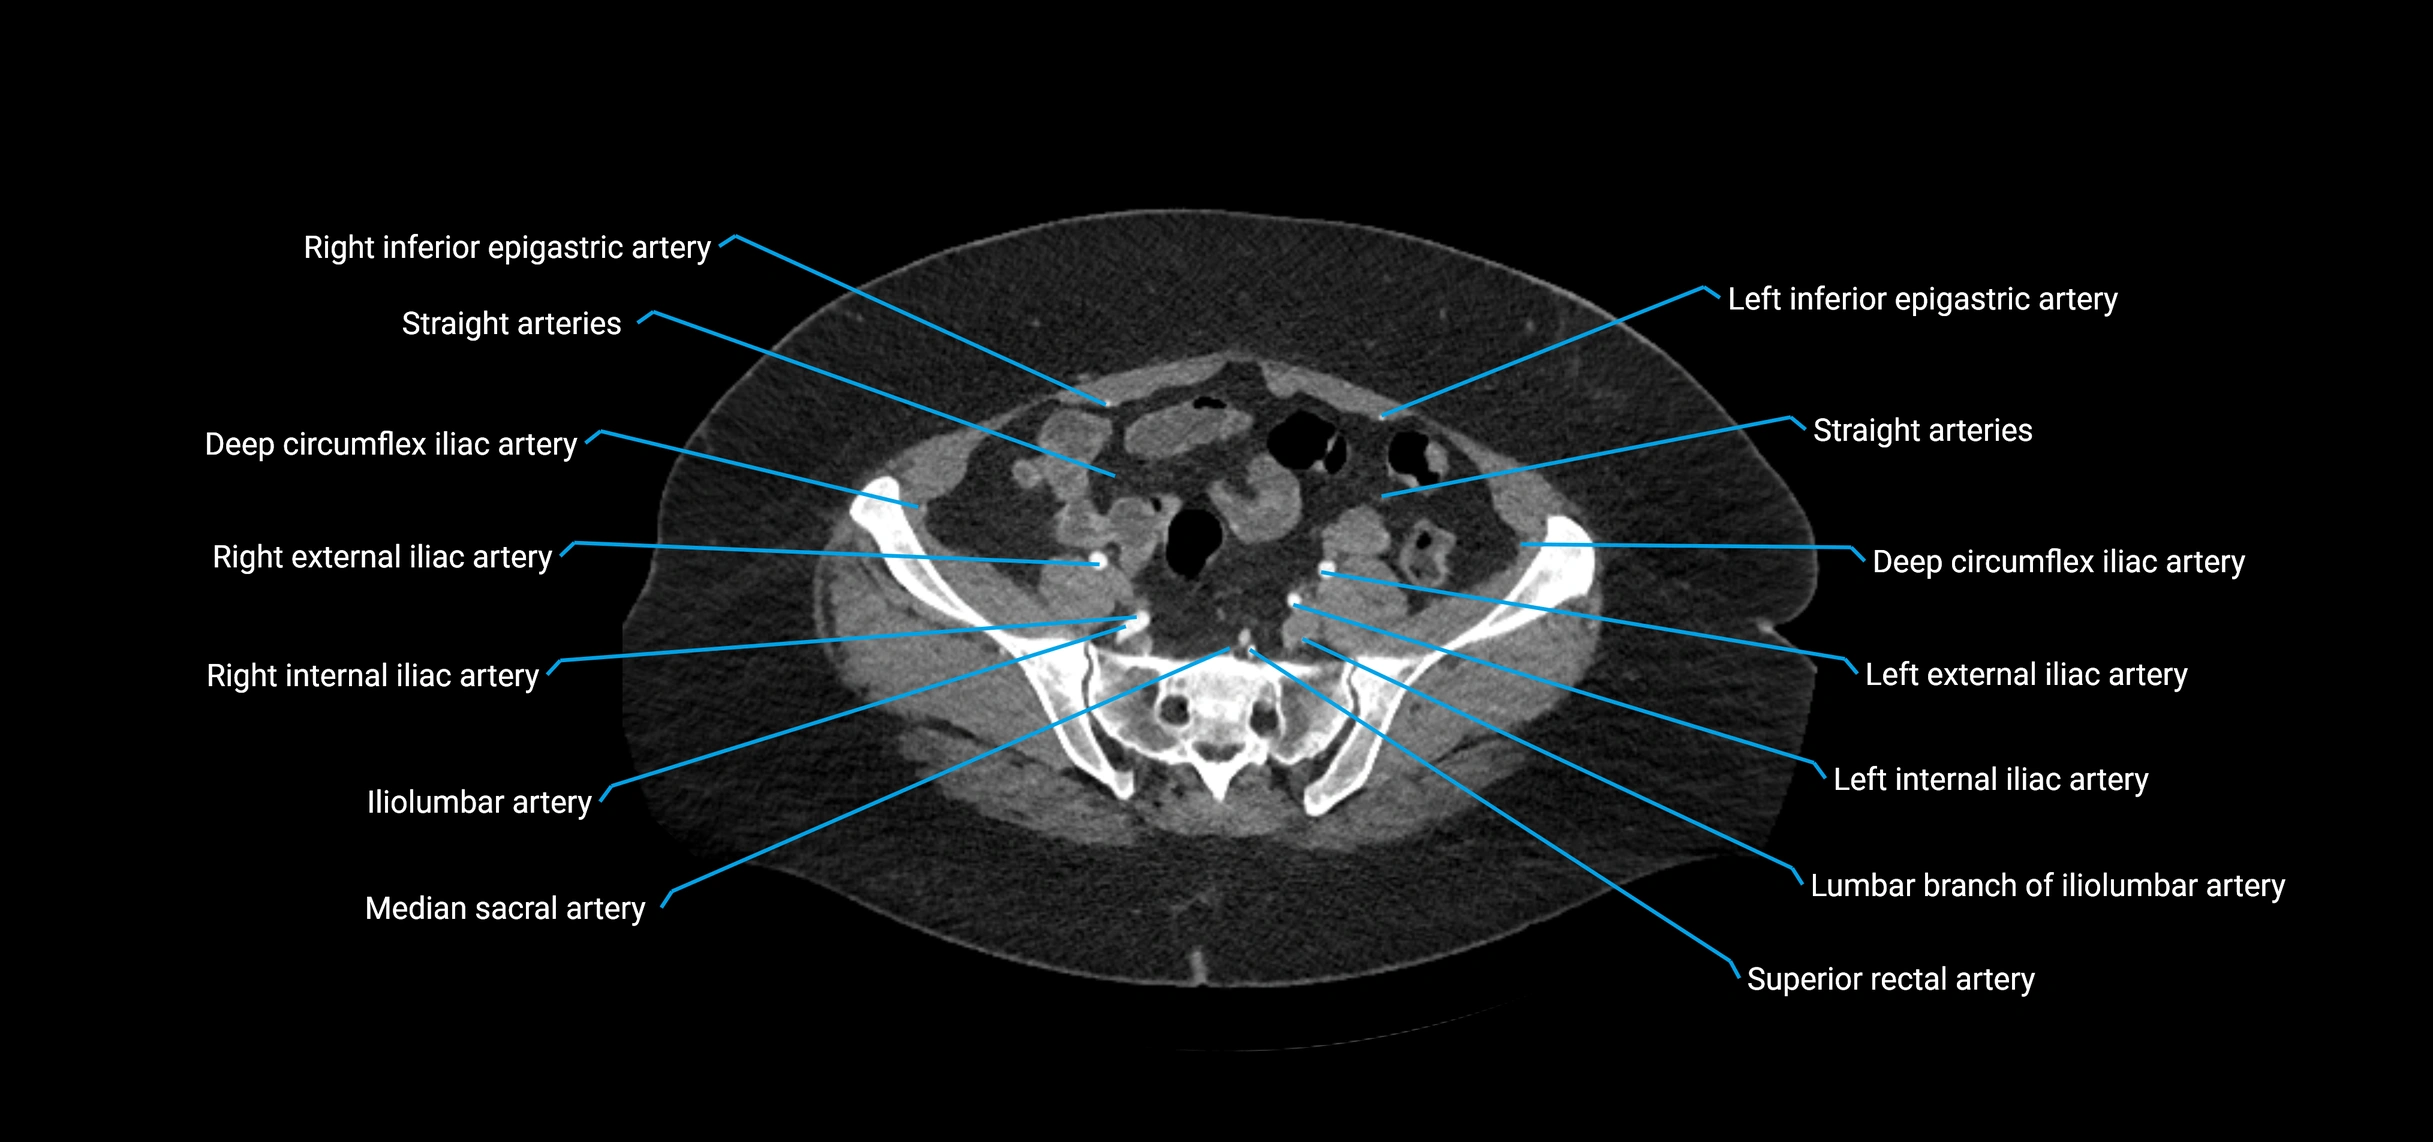

Contrast-enhanced CT (CTA):

• Gold standard for abdominal aortic imaging

• Provides excellent detail of lumen, wall, aneurysm, thrombus, and branch vessels

• Multiplanar and 3D reconstructions help in aneurysm measurement, stent graft planning, and dissection evaluation